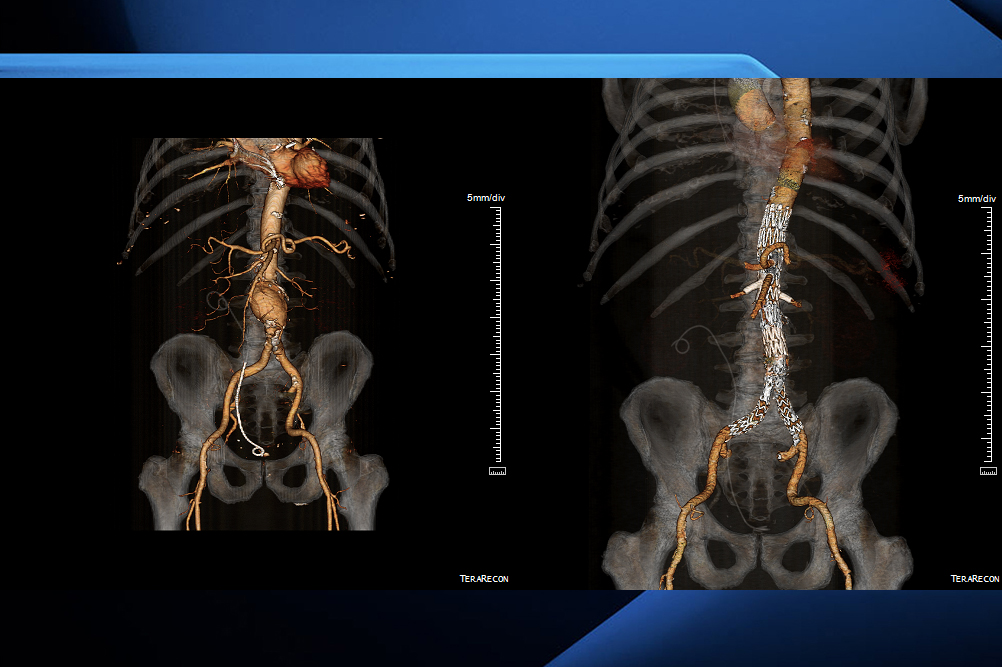

The procedure, a fenestrated endovascular aneurysm repair, or FEVAR for short, is carried out to repair extensive aneurysms in the aorta, the body’s largest artery, as well as in the chest and abdomen, LHSC officials say.

With FEVAR, LHSC officials say surgeons use a custom-made endovascular stent-graft that, with X-ray guidance, is placed in the aorta through a tiny incision near the groin roughly the size of a standard drinking straw.

“Mr. Barker’s case went up very close to all of these blood vessels that supply the major organs of the abdomen,” Landau said.

“We had a device that was custom made to incorporate all of those branch blood vessels to his major organs with additional branch stents that go into those blood vessels, (ensuring) that the entire system of stents that we put in exclude blood flow from the aneurysm.”